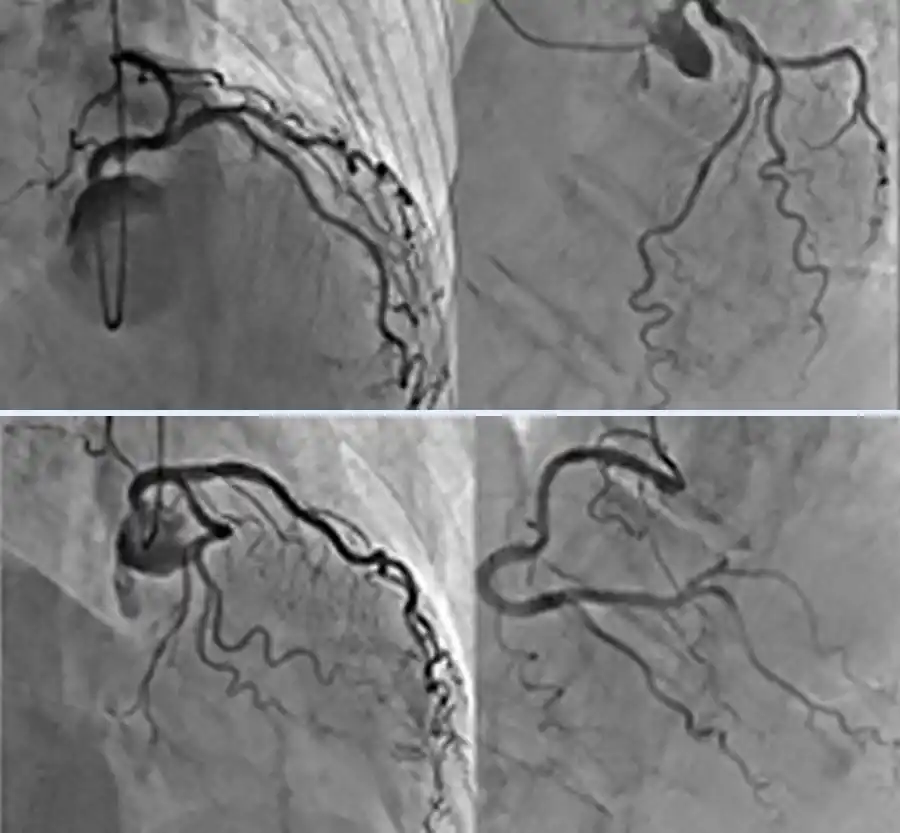

■心臓カテーテル検査

循環器科が扱う狭心症や心筋梗塞等の虚血性心疾患の患者さんの検査あるいは血管拡張術・ステント留置術・血栓溶解療法等の治療を行います。また不整脈科による心筋焼灼術(カテーテルアブレーション)も行われます。